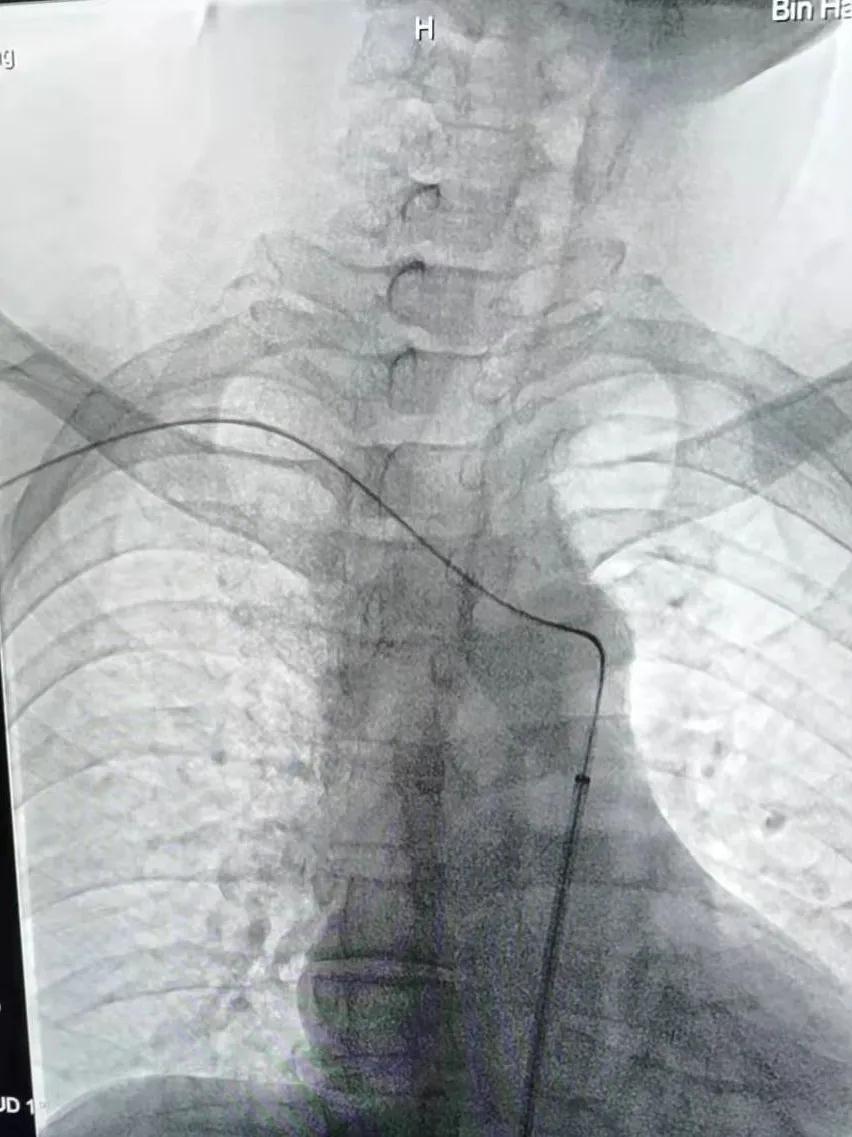

近日,濱海康達醫院成功為一位鎖骨下盜血綜合癥伴右鎖骨下動脈閉塞患者,實施DSA下右鎖骨下動脈球囊擴張+支架置入術,該手術的成功,再一次刷新了濱海康達醫院開展微創介入治療的新病種,為更多患者帶來健康福音。

家住揚州寶應的王先生,男,52歲,吸煙喝酒多年,已反復暈厥多次,先后到北京和當地醫院求診,均因病情復雜而被拒。后經親戚介紹至濱海康達醫院求診,介入科魏棟主任醫師接診后,行相關檢查并結合此前北京檢查病例資料,臨床診斷為:鎖骨下盜血綜合癥伴右鎖骨下動脈閉塞,擬實施DSA下右鎖骨下動脈造影+球囊擴張+支架植入術。